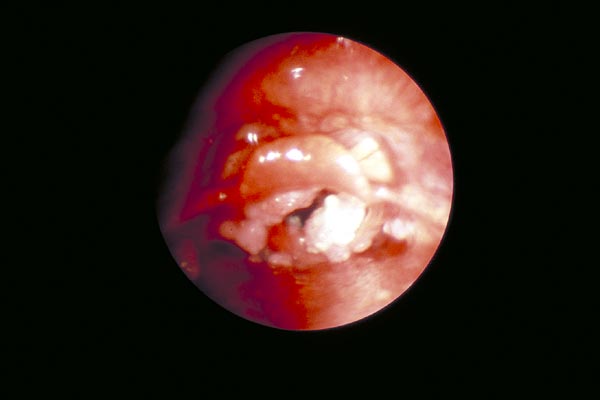

Stimmbandpolyp

|

Stimmbandkarzinom

laryngoskopieren

Laryngoskopie